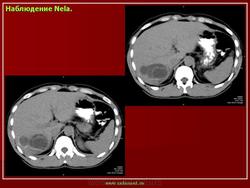

Приводим клиническое наблюдение. Больная Г- ва В.А. 35лет , жалоб не предьявляет. При профилактическом осмотре на УЗИ выявлено: по органам без особенностей, тоны сердца приглушены, пульс 79 ударов в минуту, А/Д 140/95мм.рт.ст. Живот мягкий, безболезненный. Лабораторные данные – общий анализ крови - эозинофилия, общий анализ мочи, коагулограмма в пределах возрастной нормы. При УЗИ органов брюшной полости выявлено два кистозных образования, занимающие правую долю с характерной для Э многослойной капсулой (рис 7а). КТ, МРТ уточнили кистозный характер изменений, их локализацию, наличие толстой капсулы (рис 7б). На основании комплексного анализа поставлен диагноз Э кисты.

Рис 7. Э печени а)УЗИ – кистозное образование с многослойной капсулой, эхогенной взвесью, краевым ослаблением УЗ б, в) РКТ, МРТ – кистозные образования, толстая капсула